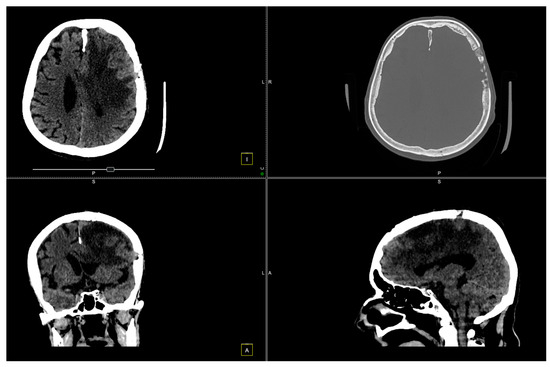

The postoperative course was favorable, with significant neurological improvement observed (Figure 5 and Figure 6).

Figure 5. CT scan conducted 7 days post-surgery.

Figure 6. CT scan conducted 14 days after the surgery.

At the 2-month follow-up check, we conducted another CT scan (Figure 7).

Figure 7. CT scan shows left paramedian frontal hypodensity, without contrast outlet.